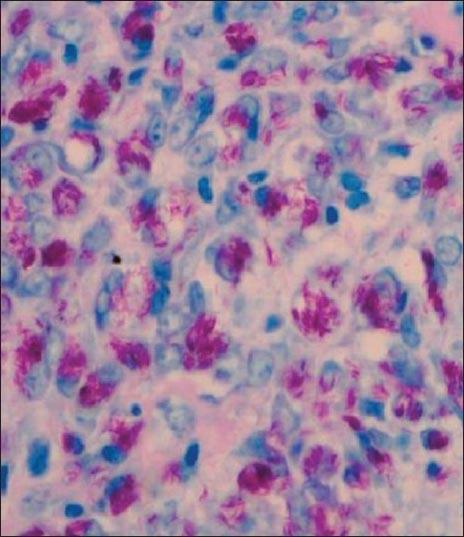

Histoid leprosy is an uncommon variant of lepromatous leprosy that usually follows treatment failure. Occasionally it occurs de novo without any history of previous inadequate or irregular treatment. We, hereby, report a case of de novo histoid leprosy in a 25-year-old man from the post-elimination area of Kashmir, where the prevalence rate of the disease was reported to be 0.17/10000 in March, 2013 (NLEP).

组织样麻风是瘤型麻风的一种罕见变异型,通常发生于治疗失败后。偶尔也会在没有任何先前治疗不足或不规范病史的情况下新发。在此,我们报告一例来自克什米尔消除地区的25岁男性新发组织样麻风病例,该地区在2013年3月报告的该病患病率为0.17/10000(国家麻风病消除项目)。